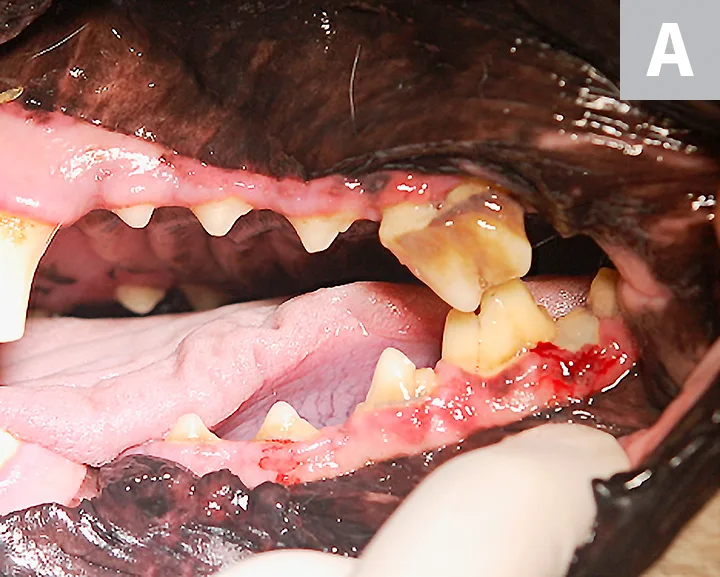

right maxillary fourth premolar of a dog showing inflammation and a root fragment extending into the oral cavity

Intraoral image of the right maxillary fourth premolar showing inflammation and a root fragment extending into the oral cavity (arrow)

After several months, the oral wound had not healed appropriately, and the patient demonstrated apparent continued discomfort, especially while eating. He was referred to a specialist for further treatment. Oral examination on referral revealed that the extraction site of the right maxillary fourth premolar was unhealed, with a root fragment extending from the inflamed gingiva (Figure 1).